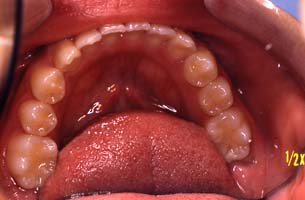

上顎

(ミラー像) | | |  | | |